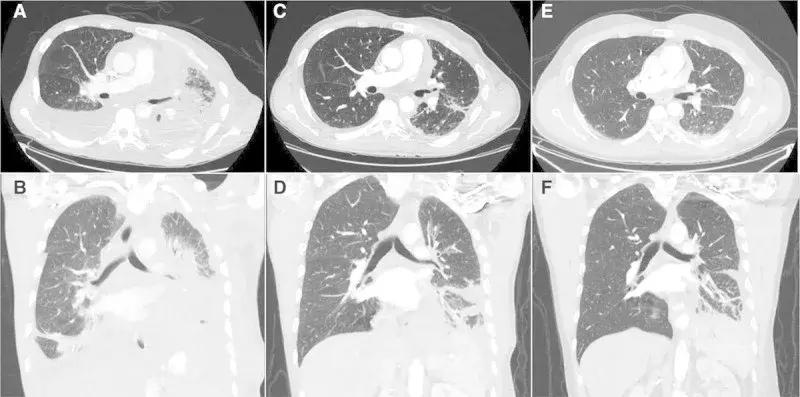

第26天(C,D)和第155天(E,F)胸部图像,肿瘤缩小77%!

大叔每天以400 mg / ㎡口服,三周后,疼痛和呼吸困难症状消失,不在需要吸氧,并且,全身的肿瘤缩小46%,胸壁5公分的病灶已看不到摸不到!脑部肿瘤大部分消退;吃药5个月,症状不断改善,全身的肿瘤缩小77%,脑转移完全消失!!!